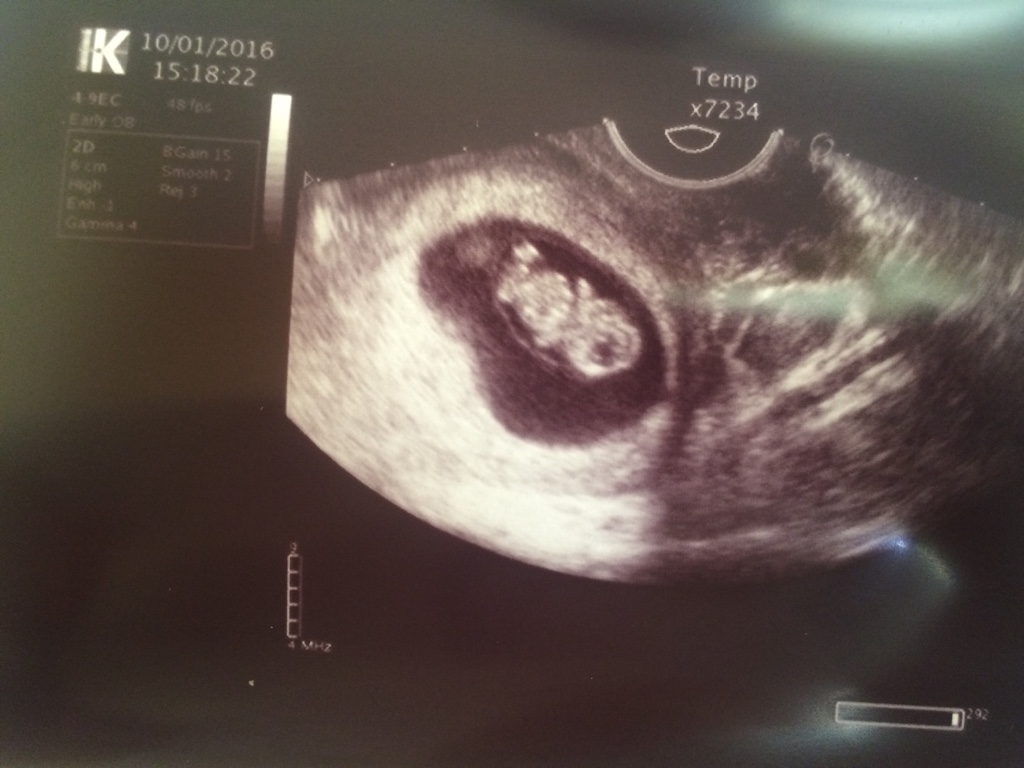

1474995167-rgwar2.jpeg

jest moje 1 cm szczęścia [emoji173]️[emoji7] serduszko cudownie bilo[emoji173]️[emoji173]️[emoji173]️[emoji173]️